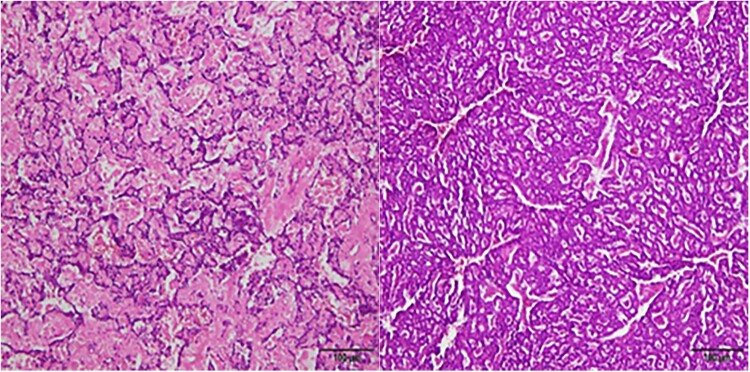

Figure 4.

Pathological findings of the pancreas. Multiple neuroendocrine tumors were consistent with G1 and G2 changes with mitotic signs < 2/10HPF. Immunohistochemical results: CgA+, Syn+, SSTR2 (part 1+, Part 3+), P53 wild type, Ki67 (2-4%).

Figure 5.

Pathological findings of the adrenal gland. The left adrenal tumor was identified as mucinous adrenocortical carcinoma, exhibiting mitotic signs > 5/50HPF and capsular invasion, without venous invasion or sinusoidal invasion. Immunohistochemical results: PCK-, CR-, MelanA±, Vim+, Syn+, CgA-, S-100-, HMB45±, β-catenin + (membrane), SOX-10-, P53wild type, Ki67+ (15%), SF1(−).